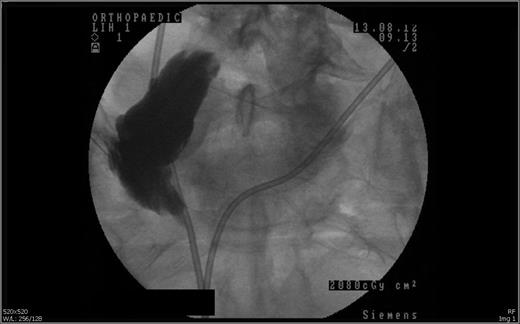

His initial blood test shows the potassium level of 9.1 mEq/l, serum urea of 20.1 mM/l, creatinine of 521 µM/l. He was immediately treated with calcium gluconate 10%, insulin-sliding scale and salbutamol nebulisers. An ultrasound scan of the renal tracts was carried out and subsequently shows bilateral hydronephrosis. Computed topography of the head revealed no intracranial bleed or infarct for the cause of paralysis. Due to his worsened renal function, a loopogram was performed and showed a stricture 4 cm proximal to the skin opening of the ileal conduit (see Fig. 1).

Loopogram revealed the stricture at 4 cm proximal to the skin opening of the conduit.

Ileal conduit strictures can be investigated through three means: computed topography urogram, loopogram and looposcopy. Due to our patient's nature of renal failure, CT urogram is not feasible. A series of X-ray was initiated after contrast liquid was injected through the stoma. In our case, it showed a stricture 4 cm proximally to the skin opening of the ileal conduit.